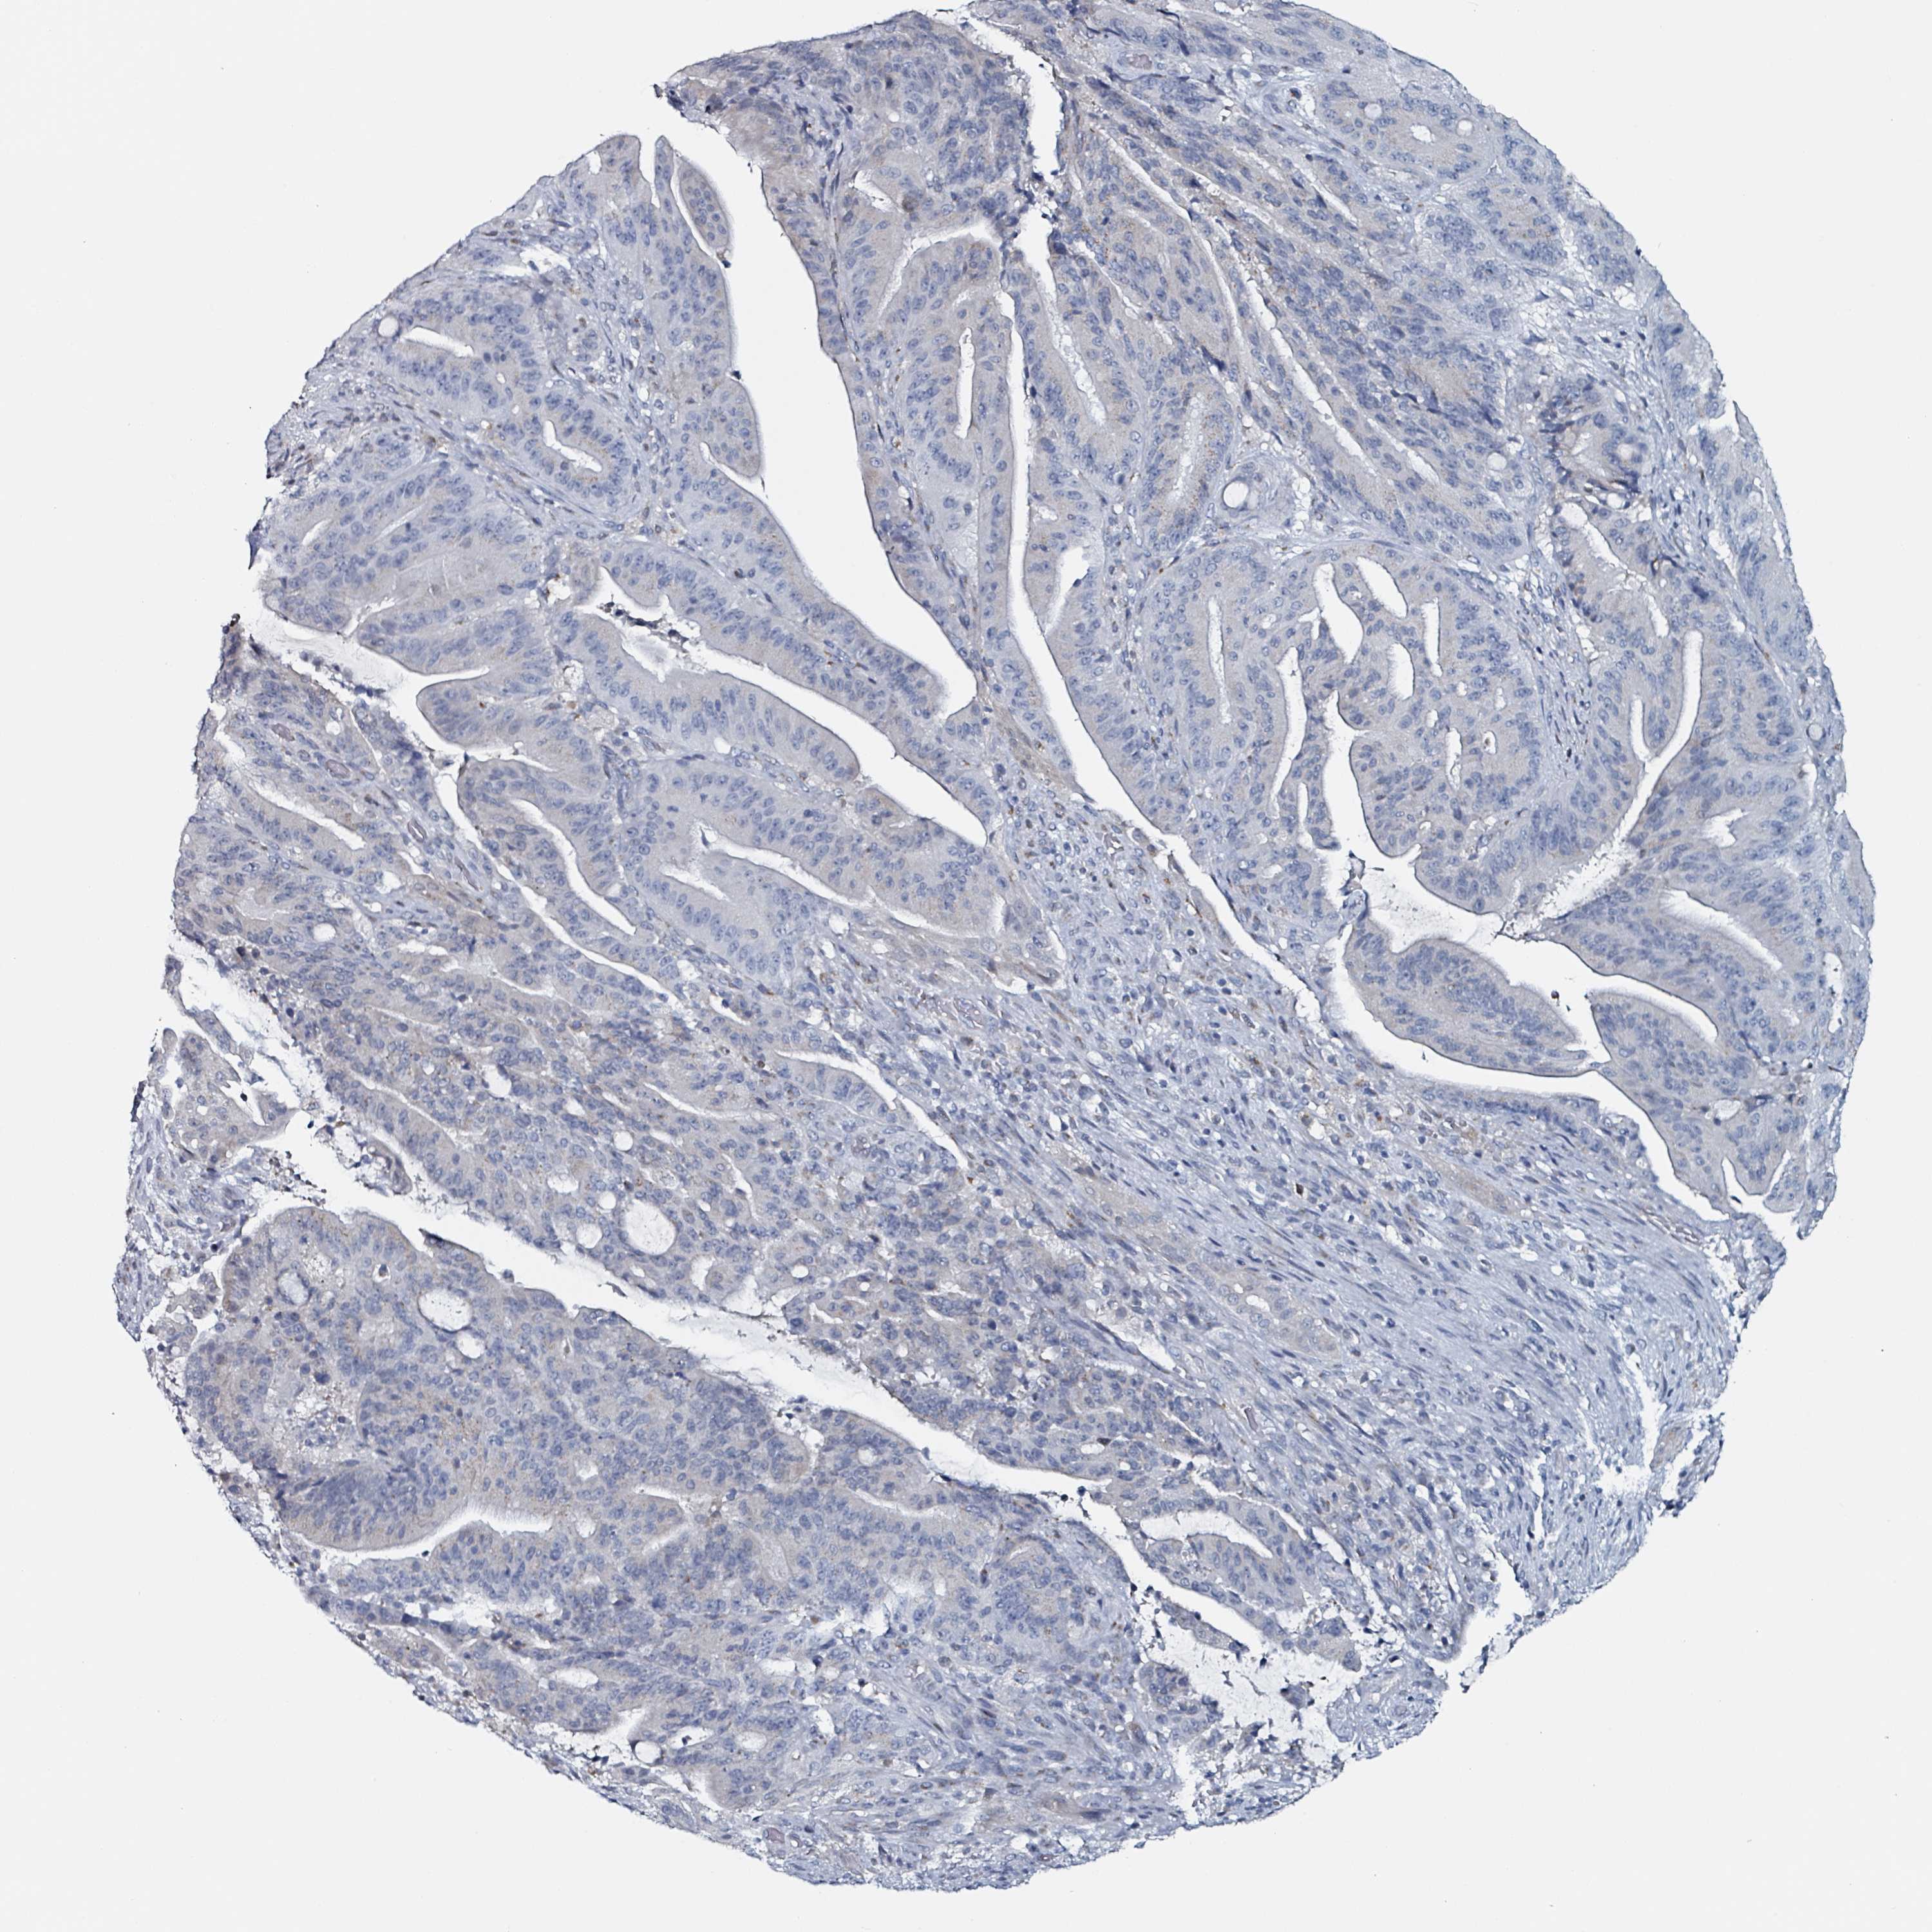

LIVER CANCER - Protein expressioni

A mouse-over function shows sample information and annotation data. Click on an image to view it in a full screen mode. Samples can be filtered based on level of antibody staining by selecting one or several of the following categories: high, medium, low and not detected. The assay and annotation is described here.

Note that samples used for immunohistochemistry by the Human Protein Atlas do not correspond to samples in the TCGA dataset.

Antibody stainingi

Antibody staining in the annotated cell types in the current human tissue is reported as not detected, low, medium, or high, based on conventional immunohistochemistry profiling in selected tissues. This score is based on the combination of the staining intensity and fraction of stained cells.

Each image is clickable and will lead to virtual microscopy that enables deeper exploration of all samples and also displays staining intensity scores, fraction scores and subcellular localization as well as patient and tissue information for each sample.

Antibody HPA051328

Staining

High

Medium

Low

Not detected

Intensity

Strong

Moderate

Weak

Negative

Quantity

>75%

75%-25%

<25%

None

Location

Nuclear

Cytoplasmic/membranous

Cytoplasmic/membranous,nuclear

Cholangiocarcinoma

Carcinoma, Hepatocellular, NOS